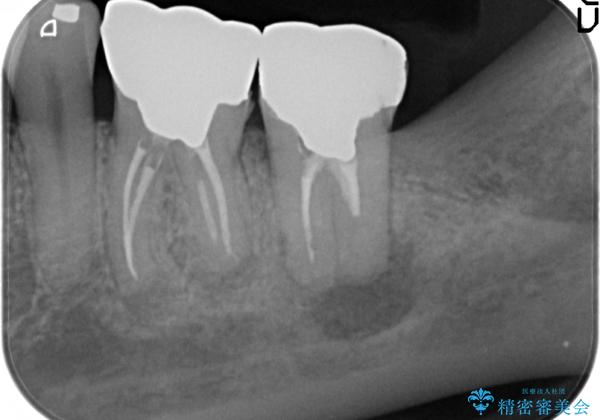

- 左下の奥歯が激しく痛むので診て欲しいといらっしゃった方の症例です。

左下7番目の歯に根尖病変を認めたため、再根管治療を行いました。

症状の消失を確認後、オールセラミッククラウンによる補綴を行いました。

今回用いたオールセラミッククラウンは、ジルコニアフレームという白い素材の上にセラミックを盛っているため審美性が非常に高いのが特徴です。

またジルコニアは人工ダイヤモンドの材料にも使われているほど高い強度を持っており、そのためオールセラミッククラウンは審美性だけでなく、奥歯やブリッジの補綴も可能とするクラウンです。